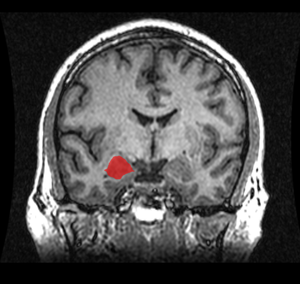

![]() موقع لوزة المخ في المخ البشري. | |

لوزة المخ amygdalaecorpus amygdaloideum؛ باللاتينية، من اللاتينية ἀμυγδαλή, amygdalē، 'almond', 'tonsil'[1])، مدرجة في تشريح گراي باسم nucleus amygdalæ، هي مجموعتين من النوى على شكل لوزة تقعان في المنطقة العميقة والوسطى داخل الفص الصدغي في المخ لدى الثدييات المتطورة، ومنها البشر.[2] أظهرت الأبحاث أن للوزة المخ دوراً أساسياً في معالجة الذاكرة، صنع القرار، وردود الفعل العاطفية، وتعتبر لوزة المخ جزءاً من الجهاز الحوفي.[3]

With advances in neuroimaging technology such as MRI, neuroscientists have made significant findings concerning the amygdala in the human brain. A variety of data shows the amygdala has a substantial role in mental states, and is related to many psychological disorders. Some studies have shown children with anxiety disorders tend to have a smaller left amygdala. In the majority of the cases, there was an association between an increase in the size of the left amygdala with the use of SSRIs (antidepressant medication) or psychotherapy. The left amygdala has been linked to social anxiety disorder, obsessive and compulsive disorders, and posttraumatic stress disorder, as well as more broadly to separation and generalized anxiety disorder.[58] In a 2003 study, subjects with borderline personality disorder showed significantly greater left amygdala activity than normal control subjects. Some borderline patients even had difficulties classifying neutral faces or saw them as threatening.[59] Individuals with psychopathy show reduced autonomic responses to instructed fear cues than otherwise healthy individuals.[60] In 2006, researchers observed hyperactivity in the amygdala when patients were shown threatening faces or confronted with frightening situations. Patients with severe social phobia showed a correlation with increased response in the amygdala.[61] Similarly, depressed patients showed exaggerated left amygdala activity when interpreting emotions for all faces, and especially for fearful faces. This hyperactivity was normalized when patients were administered antidepressant medication.[62] By contrast, the amygdala has been observed to respond differently in people with bipolar disorder. A 2003 study found that adult and adolescent bipolar patients tended to have considerably smaller amygdala volumes and somewhat smaller hippocampal volumes.[63] Many studies have focused on the connections between the amygdala and autism.[64]